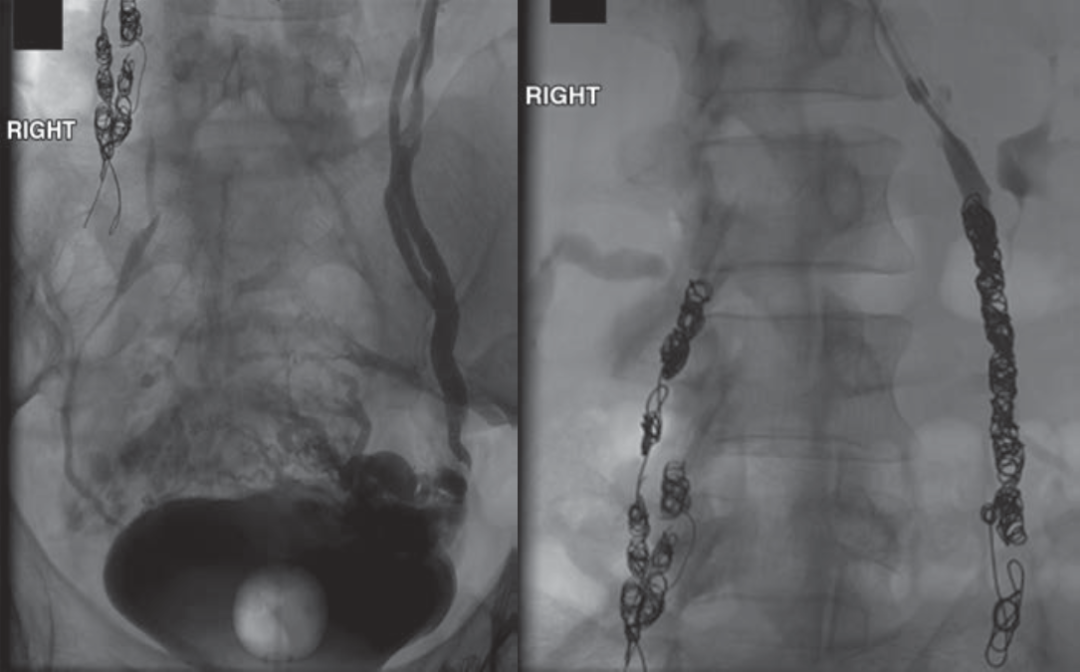

PeVD-髂内静脉同期栓塞

症状性PEP需要同期处理

中山经验:“节约型三明治技术”

入路及栓塞材料选择优化

上肢静脉(左);股静脉

血管塞;Onyx胶(昂贵)

Sandwich技术优化-节约版

GLUBRAN替代Onxy;

双股静脉入路:可调弯鞘解决反流支;

减少可控圈以及微导管使用;

减少费用;

减少照射;

减少移位;

减少复发;

需解决技术问题:液体栓塞材料溢流。

示例(D-IIV)

示例(LOV+LCV)